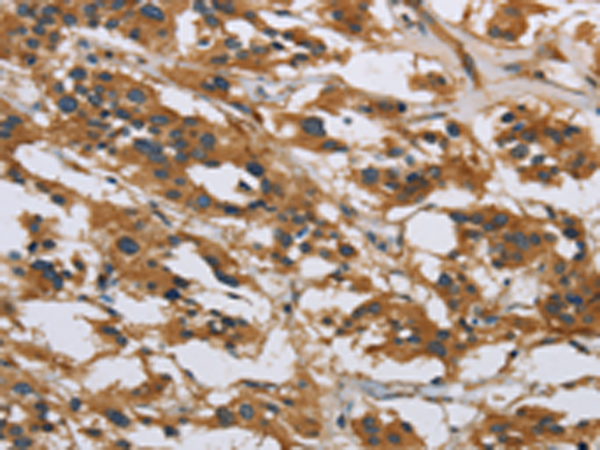

分类: 科研抗体货号: P11826别名: GGF; HGL; HRG; NDF; ARIA; GGF2; HRG1; HRGA; SMDF; MST131应用: WB,IHC反应种属: Human, Mouse